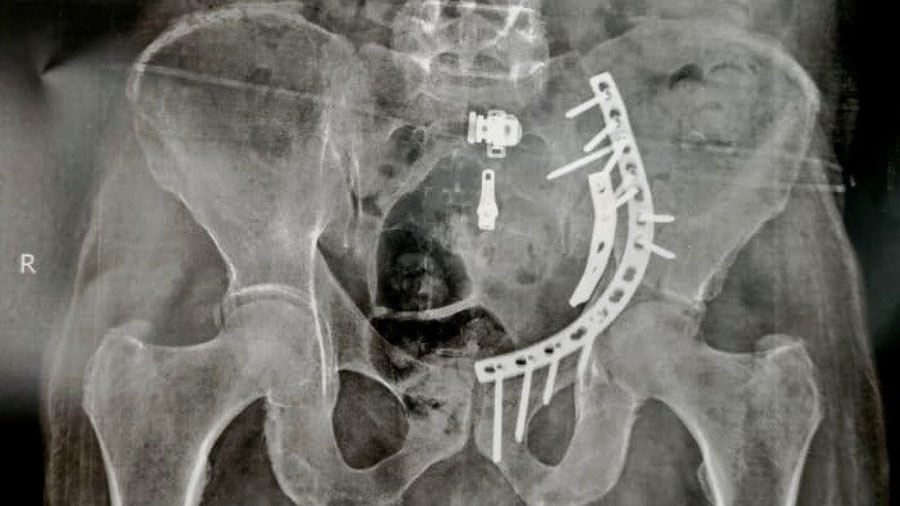

Even when the decision to operate is made, substantial variability persists in how surgery is performed. Contemporary options include traditional open reduction and internal fixation (ORIF), less invasive closed reduction and percutaneous internal fixation (CRPIF), and, in selected cases, acute total hip arthroplasty (aTHA). Each of these approaches carries distinct implications for operative risk, postoperative rehabilitation, and long-term joint survival. As a result, the question of whether to operate is rarely a simple technical decision; rather, it reflects a complex synthesis of patient biology, fracture mechanics, and health system capability.

At the same time, OM in the geriatric population is inherently demanding. Osteoporotic bone challenges fixation quality and increases the risk of implant failure. Prolonged operative times and higher blood loss place additional strain on limited physiologic reserves. Postoperative care often requires close coordination between surgical, anesthesia, geriatric, and rehabilitation teams. From both a clinical and systems perspective, OM represents a resource-intensive commitment whose success depends heavily on surgical expertise and institutional support.

Complications, defined as the occurrence of at least one adverse event, were significantly more frequent in the OM group. This increase likely reflects the burden of surgery-related problems such as infection, blood loss, implant failure, and perioperative medical complications.

The risk of conversion to total hip arthroplasty was also significantly higher following initial OM. This finding underscores the technical difficulty of achieving durable fixation in osteoporotic bone and the ongoing vulnerability of the elderly joint to mechanical failure.